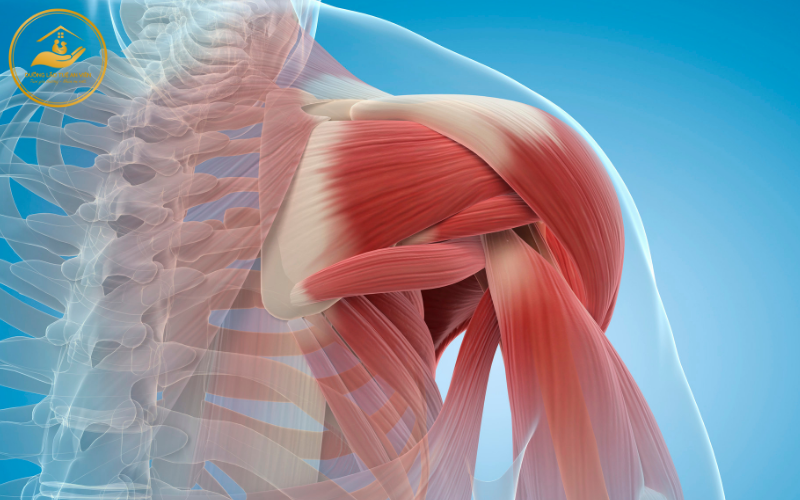

1.1 Suy giảm khối cơ nhanh theo tuổi tác

Theo thời gian, khối cơ của người cao tuổi suy giảm rõ rệt do quá trình thoái hóa và giảm tổng hợp protein. Điều này khiến người già dễ rơi vào tình trạng:

-

Yếu cơ, teo cơ

-

Giảm sức mạnh vận động

-

Khó đáp ứng các bài tập phục hồi chức năng

Trong bối cảnh này, vai trò của dinh dưỡng trong quá trình phục hồi chức năng thể hiện rõ qua việc cung cấp đủ protein và năng lượng để tái tạo mô cơ, giúp cơ thể có “nguyên liệu” phục hồi sau tập luyện.

3.1. Vai trò của dinh dưỡng trong phục hồi chức năng cơ – xương – khớp

Hệ cơ – xương – khớp là nền tảng của mọi hoạt động vận động. Dinh dưỡng hợp lý giúp:

-

Tăng khối cơ

-

Làm chậm quá trình teo cơ do tuổi tác

-

Tăng độ chắc khỏe của xương

-

Giảm đau nhức khớp khi vận động

Nếu thiếu dinh dưỡng, phục hồi chức năng dễ rơi vào vòng luẩn quẩn: tập – đau – ngại tập – suy yếu hơn. Do đó, vai trò của dinh dưỡng trong quá trình phục hồi chức năng cơ xương khớp là không thể thay thế.